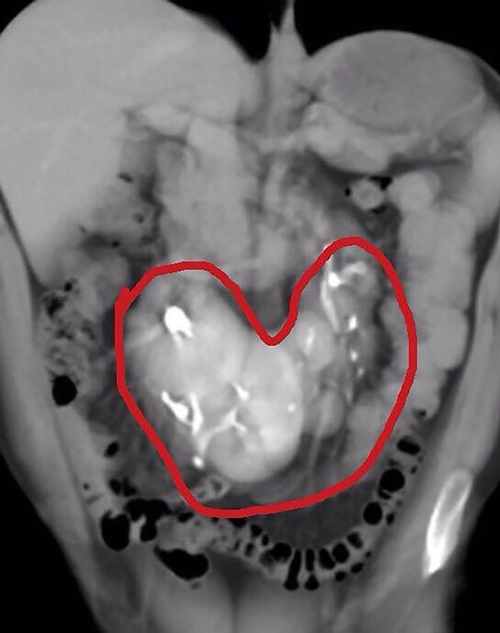

イギリスで腎臓を5つもつ男性が発見され、医師も「医学的な脅威」と驚きを見せている。フロントロウ編集部では、男性の腎臓を写したX線スキャンの写真を入手した。

ただイギリスのロブ・ブラウンさんは病院で検査を受けた時に腎臓が5つあることが発覚し、イギリスで初めての事例と認定された。過去にはインドで同じく腎臓が5つある男性が発見されており、世界で2番目の例となる。

ブラウンさんいわく検査を受けた後に病院からもう一度来るよう電話で言われ、さらなる検査を受けた末に、腎臓が5つあると報告されたという。